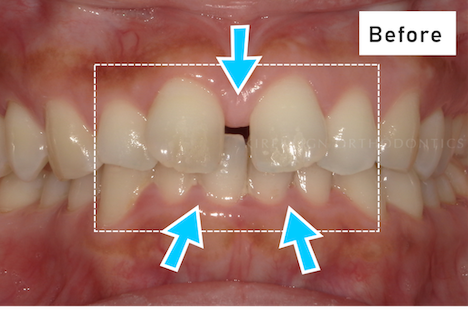

費用 396,000円(税込)

治療期間 6ヶ月

治療内容 マウスピースを用いた歯列矯正

追加処置 IPR

※保険適用外の自由診療となります。

※効果や感じ方には個人差があります。

※マウスピース矯正の主なリスク:

虫歯・歯周病・ブラックトライアングル・歯根吸収・歯肉退縮・1日20時間以上のマウスピース装着が必須・マウスピースにより痛みを感じる可能性・治療中に一時的にかみ合わせに不具合をきたす可能性・リテーナーを最低1年間は1日20時間以上装着、その後徐々に着用時間を減らし、2年目以降は夜間のみの着用推奨。